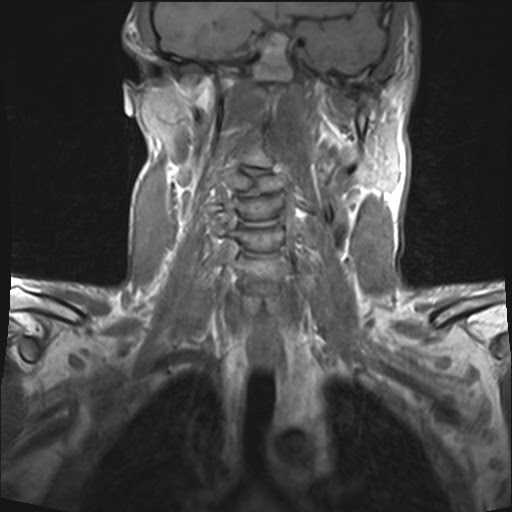

Hypoplastic Odontoid with os odontoideum and vertebral segmentation Butterfly Vertebra Mean A butterfly vertebra (sagittal cleft vertebra or anterior rachischisis) is a sagittal defect in the vertebral body caused by failure of fusion of the. A butterfly vertebra (sagittal cleft vertebra or anterior rachischisis) is a sagittal. Butterfly vertebra is an uncommon type of vertebral anomaly (sometimes referred to as a sagittal cleft vertebra or an anterior rachischisis) caused by persistent. Butterfly Vertebra Mean.